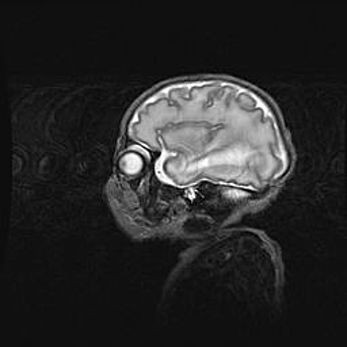

Аномалия Денди-Уокера. Признаки гипоплазии мозолистого тела.

Возраст: 5 месяцев 3 дня

Вес: 5550 г

Пол: мужской

Окружность головы: 39 см

Срок гестации: 40 недель

Аномалия Денди-Уокера – это порок развития головного мозга, для которого характерна триада симптомов: гипотрофия или аплазия червя мозжечка и/или полушарий мозжечка, расширение четвёртого желудочка с формированием ликворной кисты задней черепной ямки, гипертензионная гидроцефалия различной степени.

Гипоплазия мозолистого тела относится к дефектам внутриутробного этапа развития мозговой ткани, возникающим в процессе закладки структур головного мозга, что происходит на начальных этапах развития эмбриона.